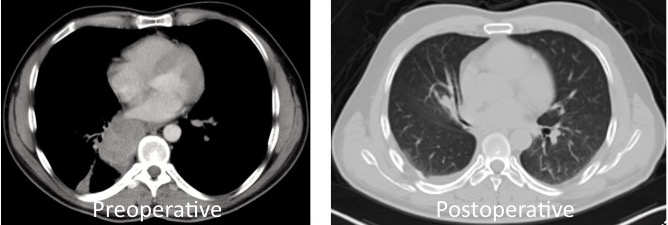

A 49-year-old male patient was operated on by the authors for a T4 (left atrium invasion) squamous cell carcinoma in the right lower lobe (Figure 1). pTNM was T4N0MO and four cycles of chemotherapy were given as adjuvant therapy. After four years of follow-up care, a chest CT showed a newly developed tumor (2.9cm) in the superior segment of the left lower lobe (Figure 2). Since there was no other increased FDG uptake in another part of the body, resection of the tumor was recommended by the Tumor Board.